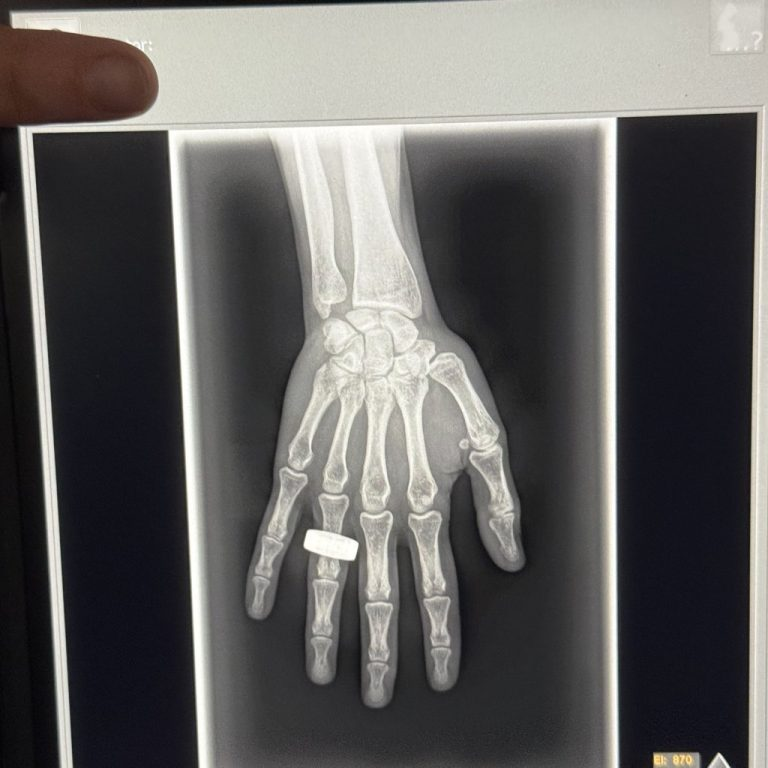

خدمه فرم ۲ آن پرتره اشعه ایکس را در ریزگرانش تقریبا در فاصله ۲۰۰ مایلی (۳۲۲ کیلومتری) بالاتر از سطح زمین بازسازی کردند. این تصویر در یک کپسول فضایی چهار نفره که با سرعت ۱۷۵۰۰ مایل در ساعت (۲۸۱۶۳ کیلومتر بر ساعت) حرکت میکرد، گرفته شده است.

در این آزمایش از یک سیستم اشعه ایکس قابل حمل که برای پروازهای فضایی اقتباس شده بود، استفاده شد و نگرانیهای اولیه مبنی بر اینکه افزایش تشعشعات پس زمینه کیفیت تصویر را به خطر میاندازد، وجود داشت.

لونی پترسن (Lonnie Petersen)، یکی از محققان در این پروژه میگوید: از نظر روشها، یکی از نگرانیهای من این بود که تشعشعات افزایش یافته پسزمینه ممکن است کیفیت تصویر را کاهش دهد و به پایینتر از استانداردهای بالینی برساند، اما اولین تصاویری که از فضا دریافت کردهایم، به نظر میرسد که کیفیت عالی است. من برای تجزیه و تحلیل بیشتر مجموعه کامل تصاویر بسیار هیجانزده هستم.

خدمه فرم ۲ با اتکا بر تصویر اشعه ایکس موفق از دست خود، این فناوری را با گرفتن تصاویر تشخیصی از ساعد، لگن، شکم و قفسه سینه بیشتر نشان دادند. آنها همچنین از اشعه ایکس برای تصویربرداری الکترونیک استفاده کردند و پتانسیل آن را برای تشخیص سختافزاری بررسی کردند.